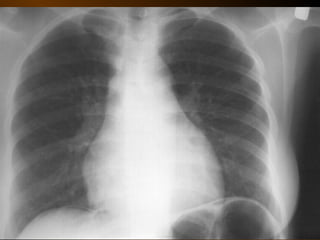

KHÍ TỰ DO

TRONG KHOANG PHÚC MẠC

NGUYÊN NHÂN

thủng tạng rỗng

nguồn gốc xuyên phúc mạc

nguồn gốc trong phúc mạc

10 – 15% thủng tạng rỗng → không thấy hơi tự do ổ bụng